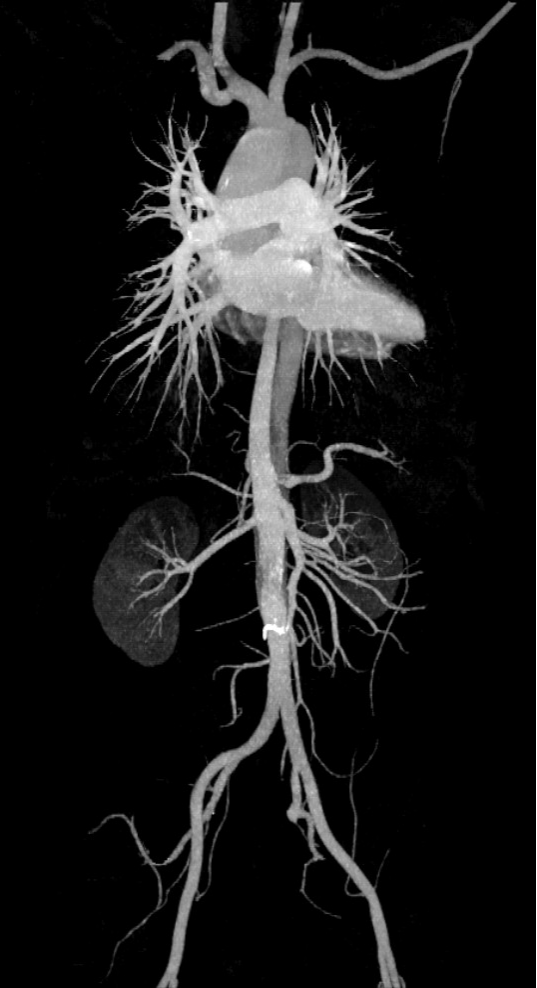

全身各部位血管造影:Incisive CT可以轻松实现大范围CT血管造影(CTA),准确了解血管及相关脏器的形态结构,评估血管及脏器功能,准确判断出血,栓塞、血管瘤、血管畸形、狭窄及肿瘤供血情况,为临床治疗提供极大帮助。

▲ 头颈部CTA、硬化斑块清晰显示

▲ 胸腹部CTA-主动脉夹层一目了然